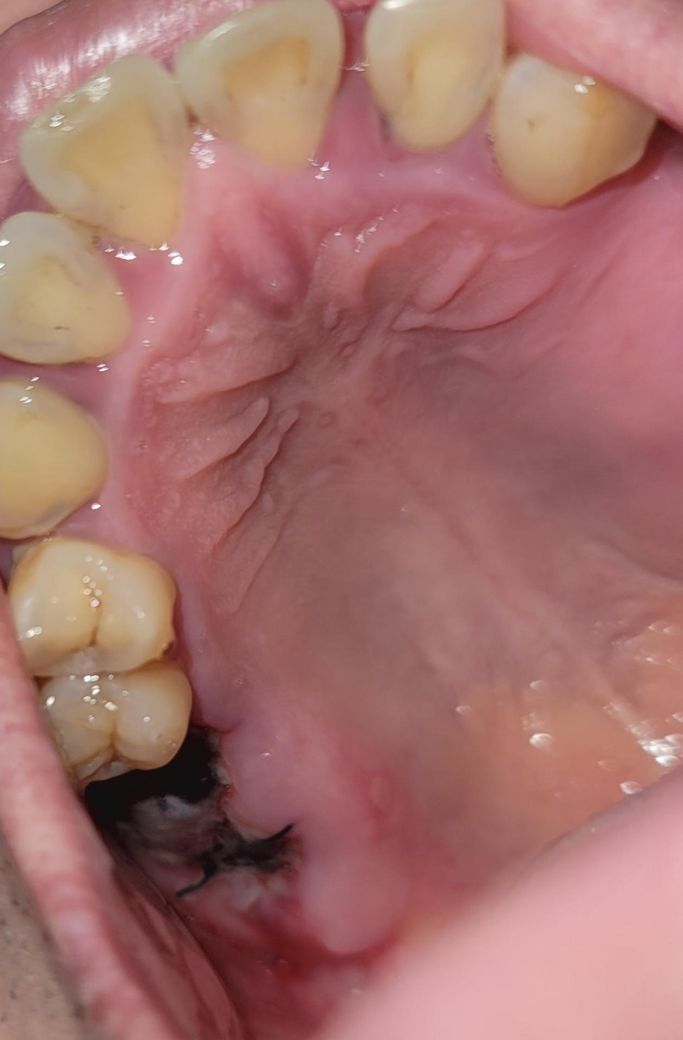

오른쪽 어금니 발치 후 피떡(혈병)이 잘 생성중 인가요?

치성 부비동염으로 인해 오른쪽 어금니 2개 발치하고

꿰멘지 3일차구요. 발치 후 구멍이 뚫려서 꿰멤

피떡이 잘 생성 되어 있는지 궁금합니다 (사진첨부)

• 1번 째 사진

피떡(혈병)은 원래 발치 후 1~2일차에 흡수되어 안보입니다. 현재 사진상으론 별다른 치유에 표면상으론 문제는 없어보입니다.

사진상을ㅇ 보면 발치한곳 잇몸이 잘 아물고 잇는거 같습니다. 자극만 가지 않도록 해주시면될것같습니다.